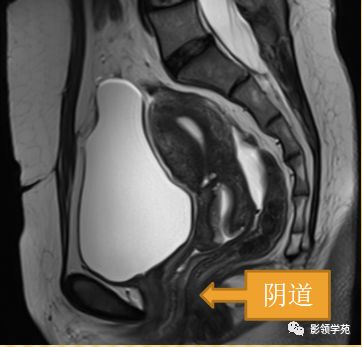

阴道壁

阴道粘膜 为复层鳞 状上皮

T1WI 呈中等稍低信号

T2WI内带:高信号(上皮、粘液)

外带 :低信号

正常MR表现:卵巢和输卵管

卵巢:轴位和冠状面显示较佳,T1WI为中等或稍低信号,T2WI可因多个卵泡结构表现为高信号,但其间质部分仍呈稍低信号

输卵管:无法显示